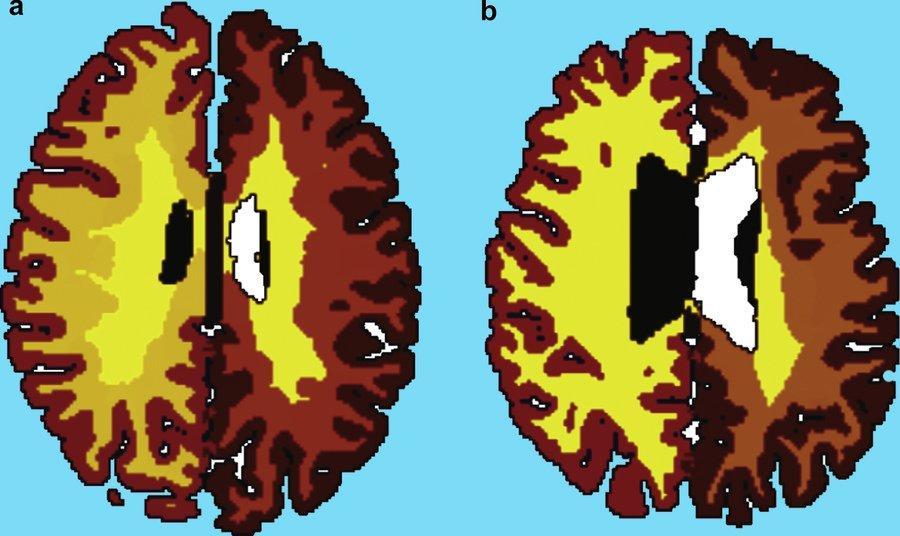

How Obesity Could Age Your Brain 10 Additional Years by Middle Age http://bit.ly/2aWDbvL pic.twitter.com/Yc6GPKBHtp